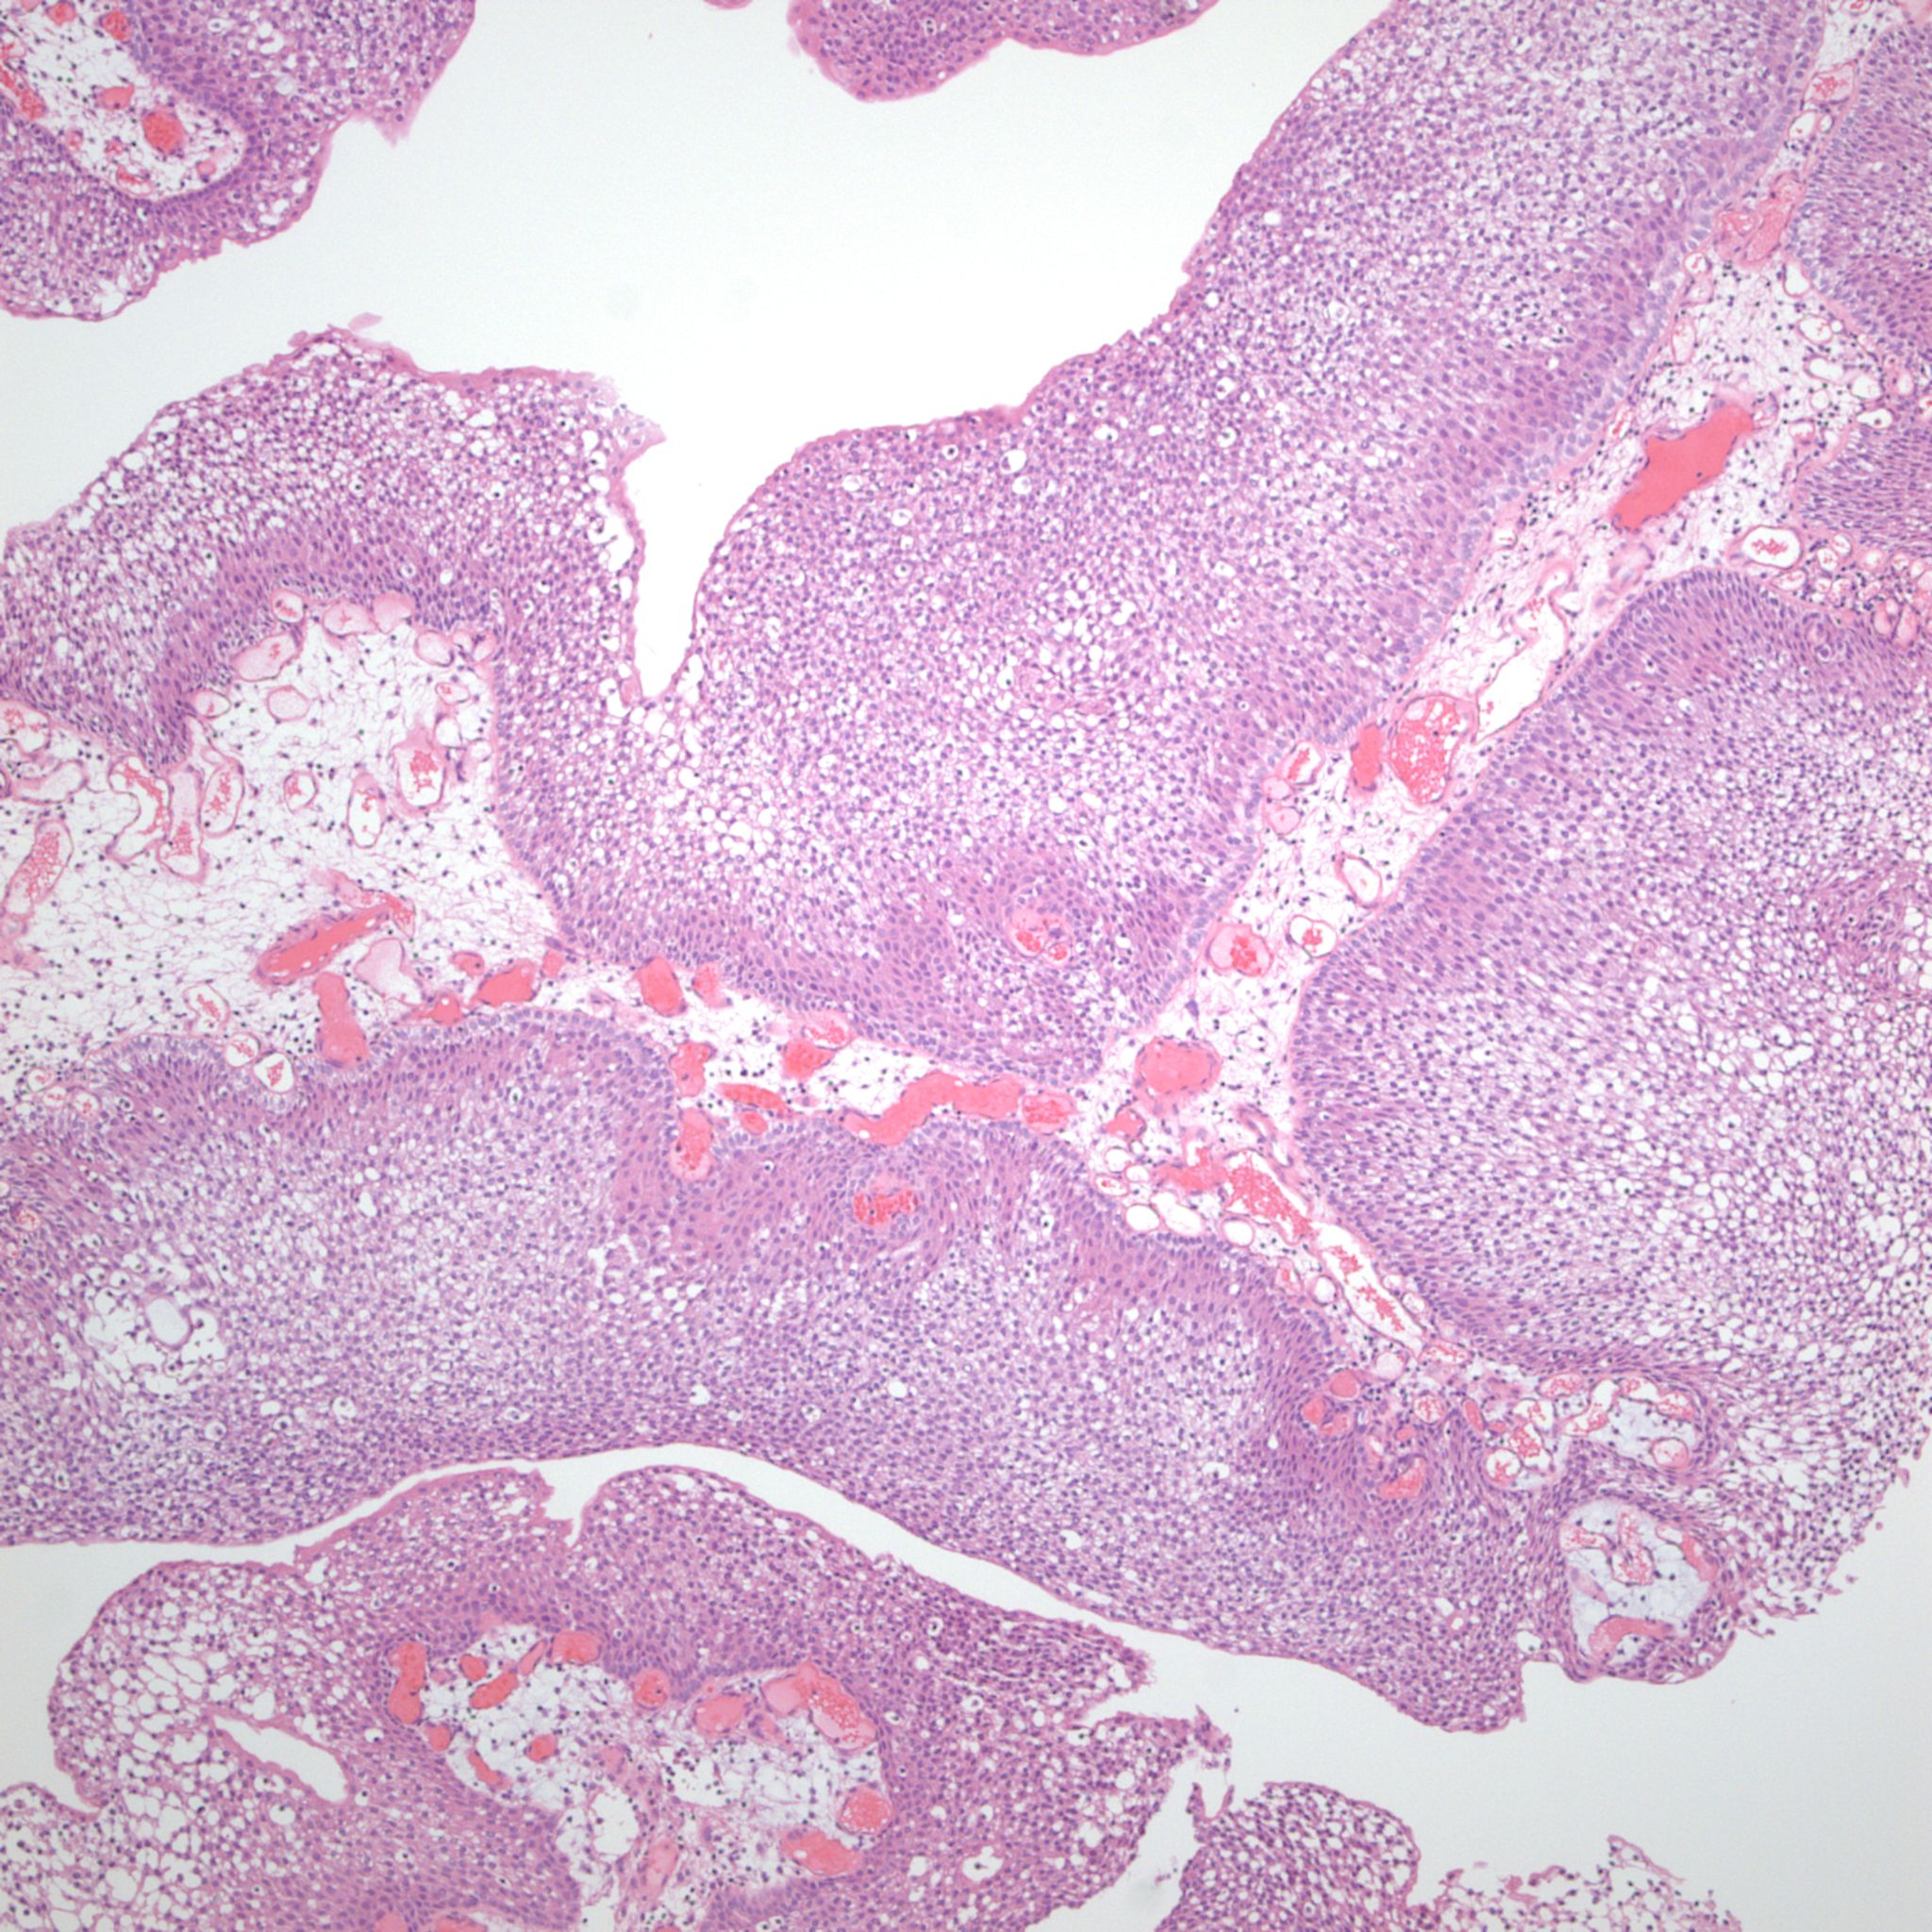

Bladder Papillary Lesions

Case ID: 315